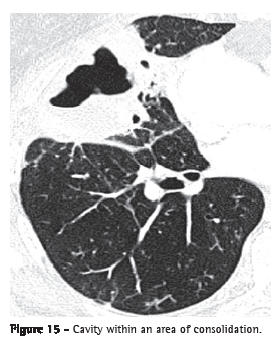

Cavitation (cavidade or escavação)Cavities are gas-filled spaces, with or without air-fluid level, within a nodule, mass or pulmonary consolidation. They are typically produced by the expulsion or drainage of a necrotic part through the airway (Figure 15) or to the pleural space. The walls of a cavity are usually irregularly outlined and measure over 1 mm in thickness. The word "cavity" is not synonymous with "abscess". Although the term "cavitation" can be translated to Portuguese as cavitação or escavação, the term cavitação has a different meaning in Portuguese and therefore should not be used as a synonym for escavação in this context.(7)